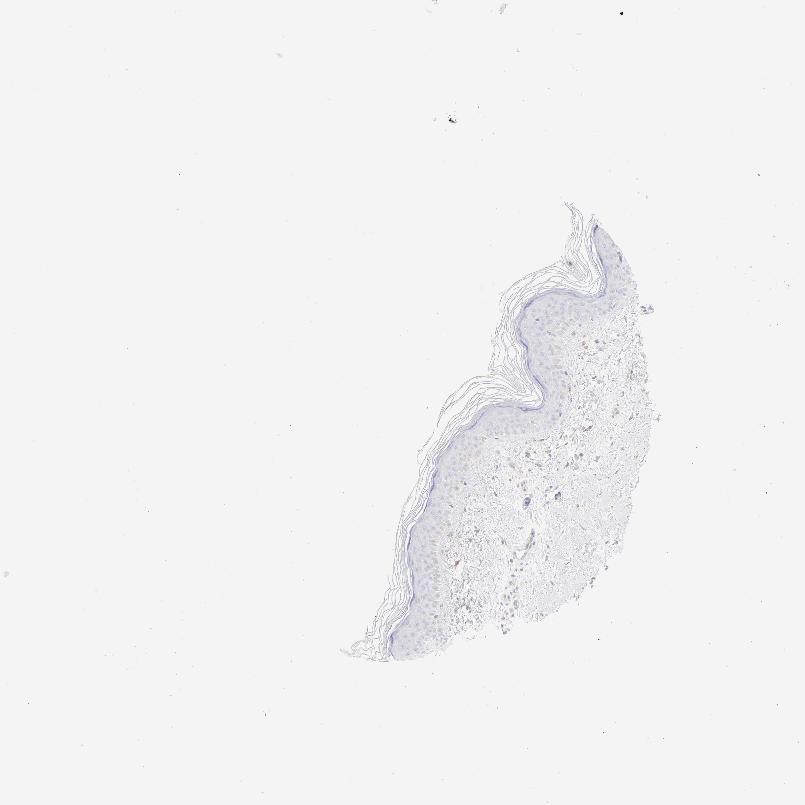

TISSUE PRIMARY DATA SKIN Show tissue menu

SKIN 1 - Antibody stainingi

Antibody staining in the annotated cell types in the current human tissue is reported as not detected, low, medium, or high, based on conventional immunohistochemistry profiling in selected tissues. This score is based on the combination of the staining intensity and fraction of stained cells.

Each image is clickable and will lead to virtual microscopy that enables deeper exploration of all samples and also displays staining intensity scores, fraction scores and subcellular localization as well as patient and tissue information for each sample.

SKIN 2 - Antibody stainingi